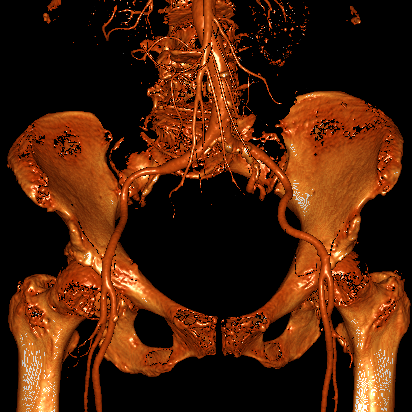

血管入路评估:双侧股动脉细小且分叉高,最窄处不到5mm,不满足可用TAVR器械对于股动脉入路最小径线的要求。患者锁骨下动脉、颈动脉同样细小,无法作为替代入路。患者升主动脉瘤样扩张,经升主动脉入路风险极高。

经TAVR团队谨慎分析、讨论后,认为本例患者升主动脉瘤样扩张、横位心,如采用自展式瓣膜进行TAVR,发生升主动脉损伤、瓣膜移位甚至瓣膜栓塞等严重并发症的风险高,采用球扩式瓣膜进行TAVR是更合理的选择。因患者外周动脉细小,经股动脉、经锁骨下动脉或经颈动脉TAVR均不可行,同时因升主动脉瘤样扩张,经升主动脉TAVR风险极高,而经腔静脉入路是可行的选择。因此,团队决定经由腔静脉至腹主动脉建立手术入路,并采用纽脉医疗球扩式Prizvalve经导管主动脉瓣系统实施TAVR。